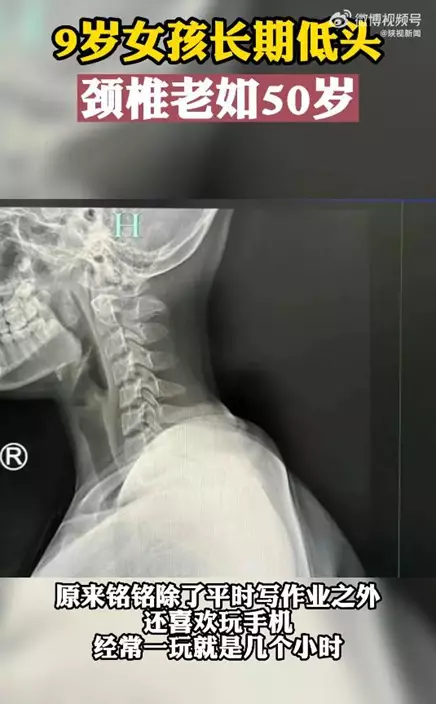

浙江杭州一名9歲女孩銘銘最近常出現脖子酸痛、手指發麻等症狀。醫生檢查後發現她的頸椎已老化如50歲長者,人的正常頸椎是呈正「C」形,而女童的頸椎弧度往反方向彎曲變成「一條直線」。原來,銘銘除了平時寫功課外,還沉迷於玩手機,經常一玩就是幾個小時,因此導致了嚴重的脊椎病,醫生藉此提醒各位家長,一定要關注子女的脊椎健康問題。